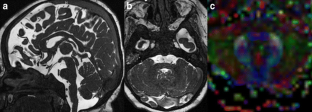

Diffusion tensor imaging (DTI) is an advanced MR technique that provides qualitative and quantitative information about the micro-architecture of white matter. DTI and its post-processing tool fiber tractography (FT) have been increasingly used in the last decade to investigate the microstructural neuroarchitecture of brain malformations. This article aims to review the use of DTI and FT in the evaluation of a variety of common, well-described brain malformations, in particular by pointing out the additional information that DTI and FT renders compared with conventional MR sequences. In addition, the relevant existing literature is summarized.